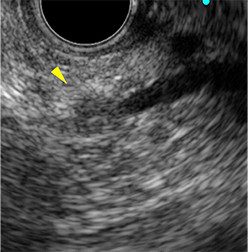

急性胆嚢炎で受診

超音波内視鏡下胆嚢ドレナージ

十二指腸から

胆嚢にステント留置